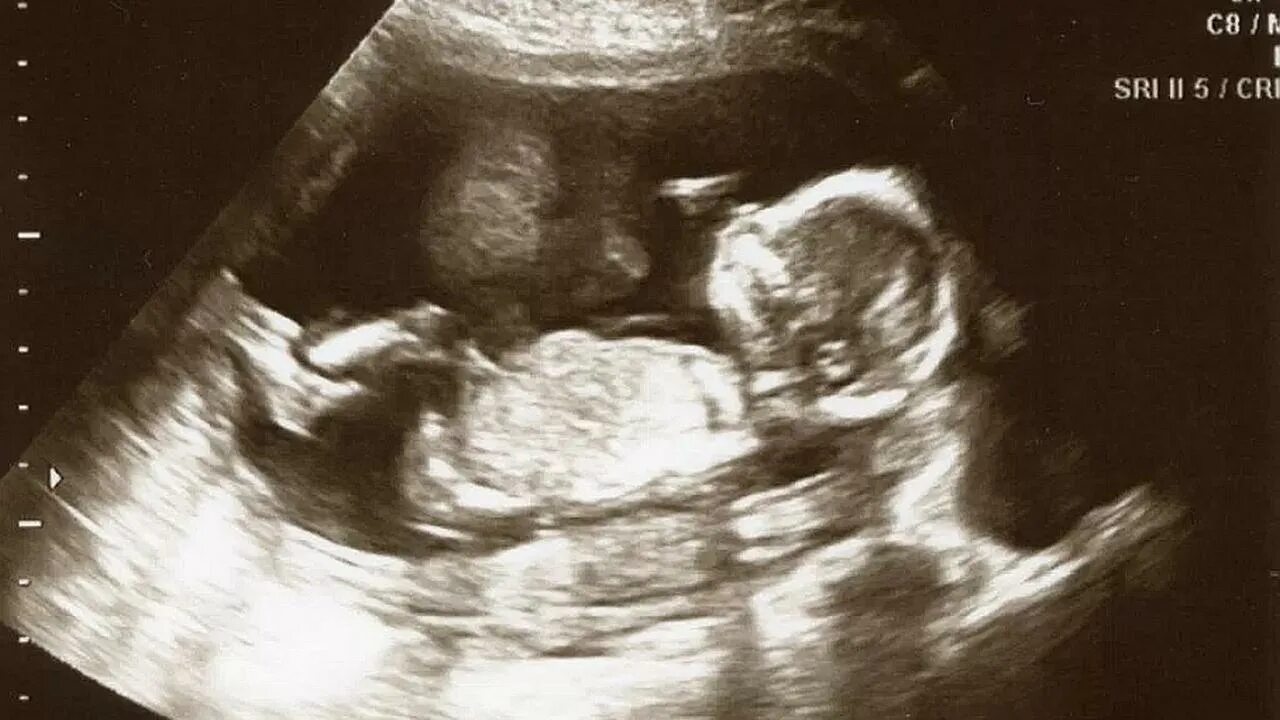

Как выглядит 16 неделя беременности фото